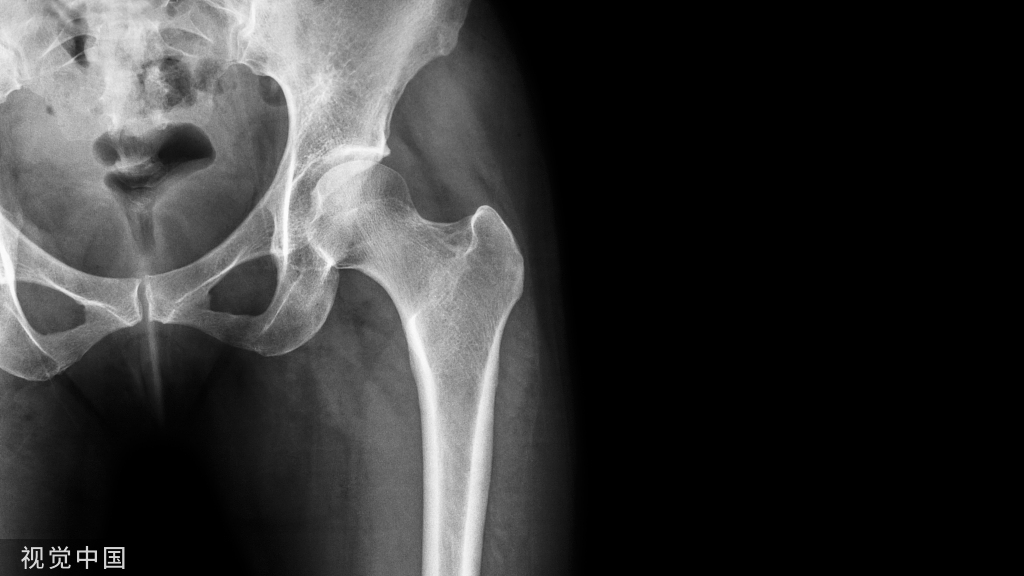

患者,男,60 岁,外伤后致右髋部肿痛,活动受限,无昏迷呕吐。

外伤后 X 线片显示:右股骨粗隆粉碎性骨折

体格检查:右髋部软组织肿胀明显,右股骨粗隆处压痛明显,患肢短缩、外旋畸形,活动受限。

临床诊断:右股骨粗隆粉碎性骨折。

治疗经过:入院后行持续右下肢骨牵引,牵引五天后行 PFNA 内固定术。

手术后 X 线片

术后 21 个月 X 线片:

患者术后一年半有余,要求去除内固定物来院,未诉不适,大意了,术前阅片不仔细,术中拆除锁钉、螺旋刀片和尾帽,拔主钉后傻眼了 —— 只拔出了上三分之一 ,回头再看片子才发现主钉刚好在螺旋刀片处断裂了。